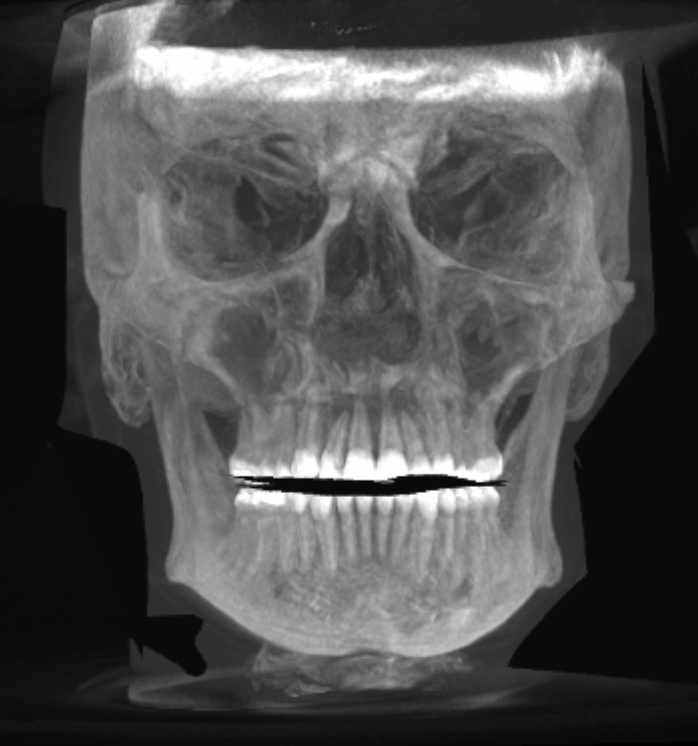

Rate this CT scan (profile, forward, 45deg)

soft tissue removed. tell me how my bones look.

narrow jaw, and kinda short chin.

you're not recessed, frankfurt plane is okay. gonions are a little bit high but not a big problem.

gonions are outward, that is really important.

is it my impression or do you got downward growth?

>is it my impression or do you got downward growth?

maybe. i have gummy smile. jaw surgeon said it seemed mostly due to soft tissue, but offered le fort 1 anyway to keep my options option. i'm tryna to decide best option and see if jaw surgery is needed for other reasons too... two birds, one stone etc